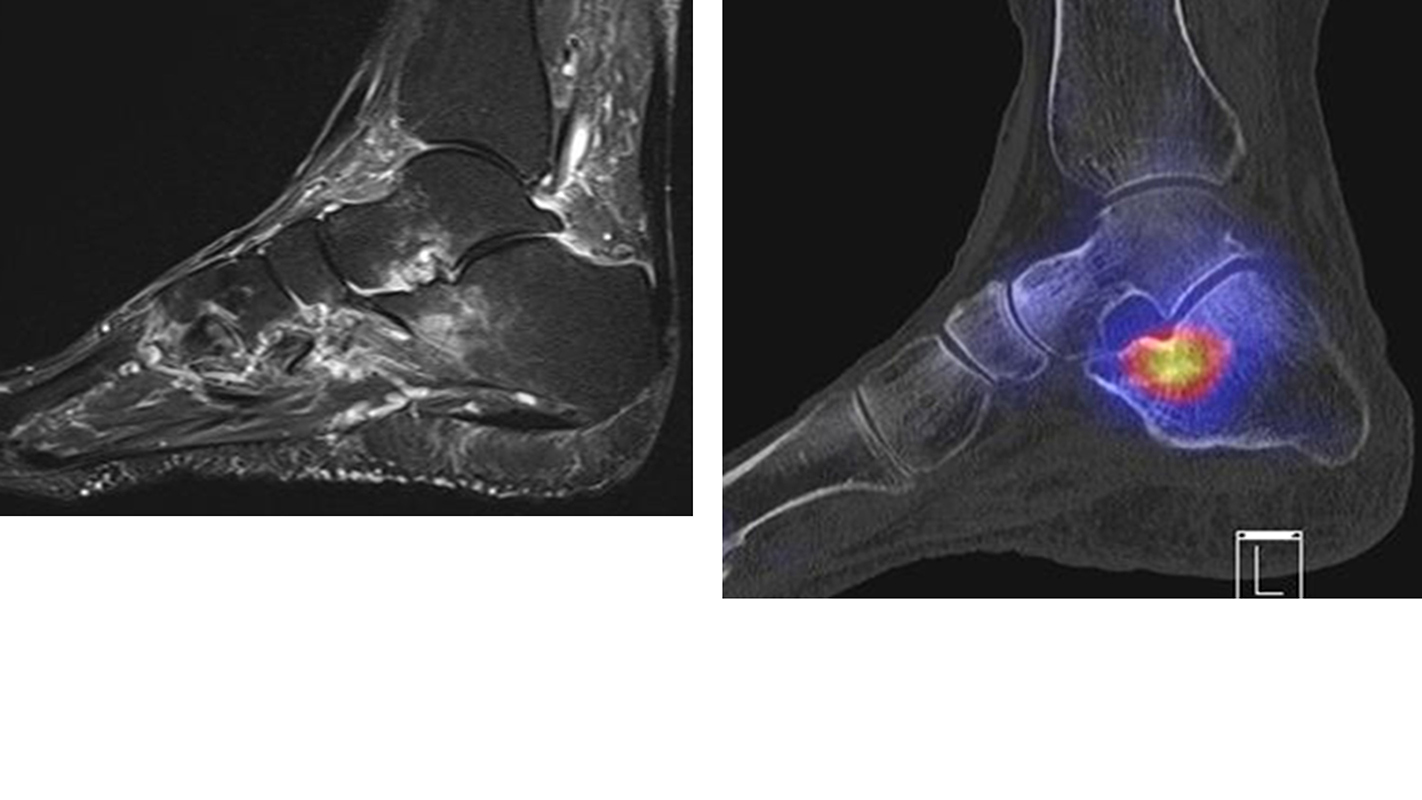

Abbildung 9.1.a bis d: Insuffizienzfraktur bei einer Patientin mit bekannter Osteoporose und chronischen rechtsseitigen Fußschmerzen. Es wurden 3 MRT-Untersuchungen in 9 Monaten durchgeführt (!), welche wechselnde Ödeme in den Fußwurzelknochen zeigten ohne dass eine eindeutige Diagnose formuliert wurde. Die SPECT/CT zeigt den typischen Aspekt einer Insuffizienzfraktur im vorderen Abschnitt des Calcaeus mit hypermetabolen linearen intraspongiösen Verdichtungen; im MRT (5 Wochen vor der SPECT/CT angefertigt) "nur" ödematöse Knochenmarkveränderungen.